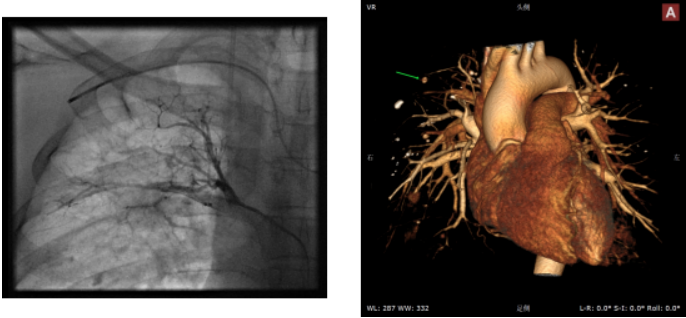

患者男性,65岁,⻋祸、外伤后出现咯⾎13天,⼤咯⾎,肋骨骨折,胸部损伤,左肺下叶⽀⽓管扩张伴感染。于我院就诊。急诊CT血管成像和VR,可见肺动脉分支与PAP相通,但肺动脉主干造影未见PAP,将导管置于左下叶肺动脉,造影可见动脉瘤。予肺动脉放置弹簧圈,造影显示PAP消失,后⽌⾎。